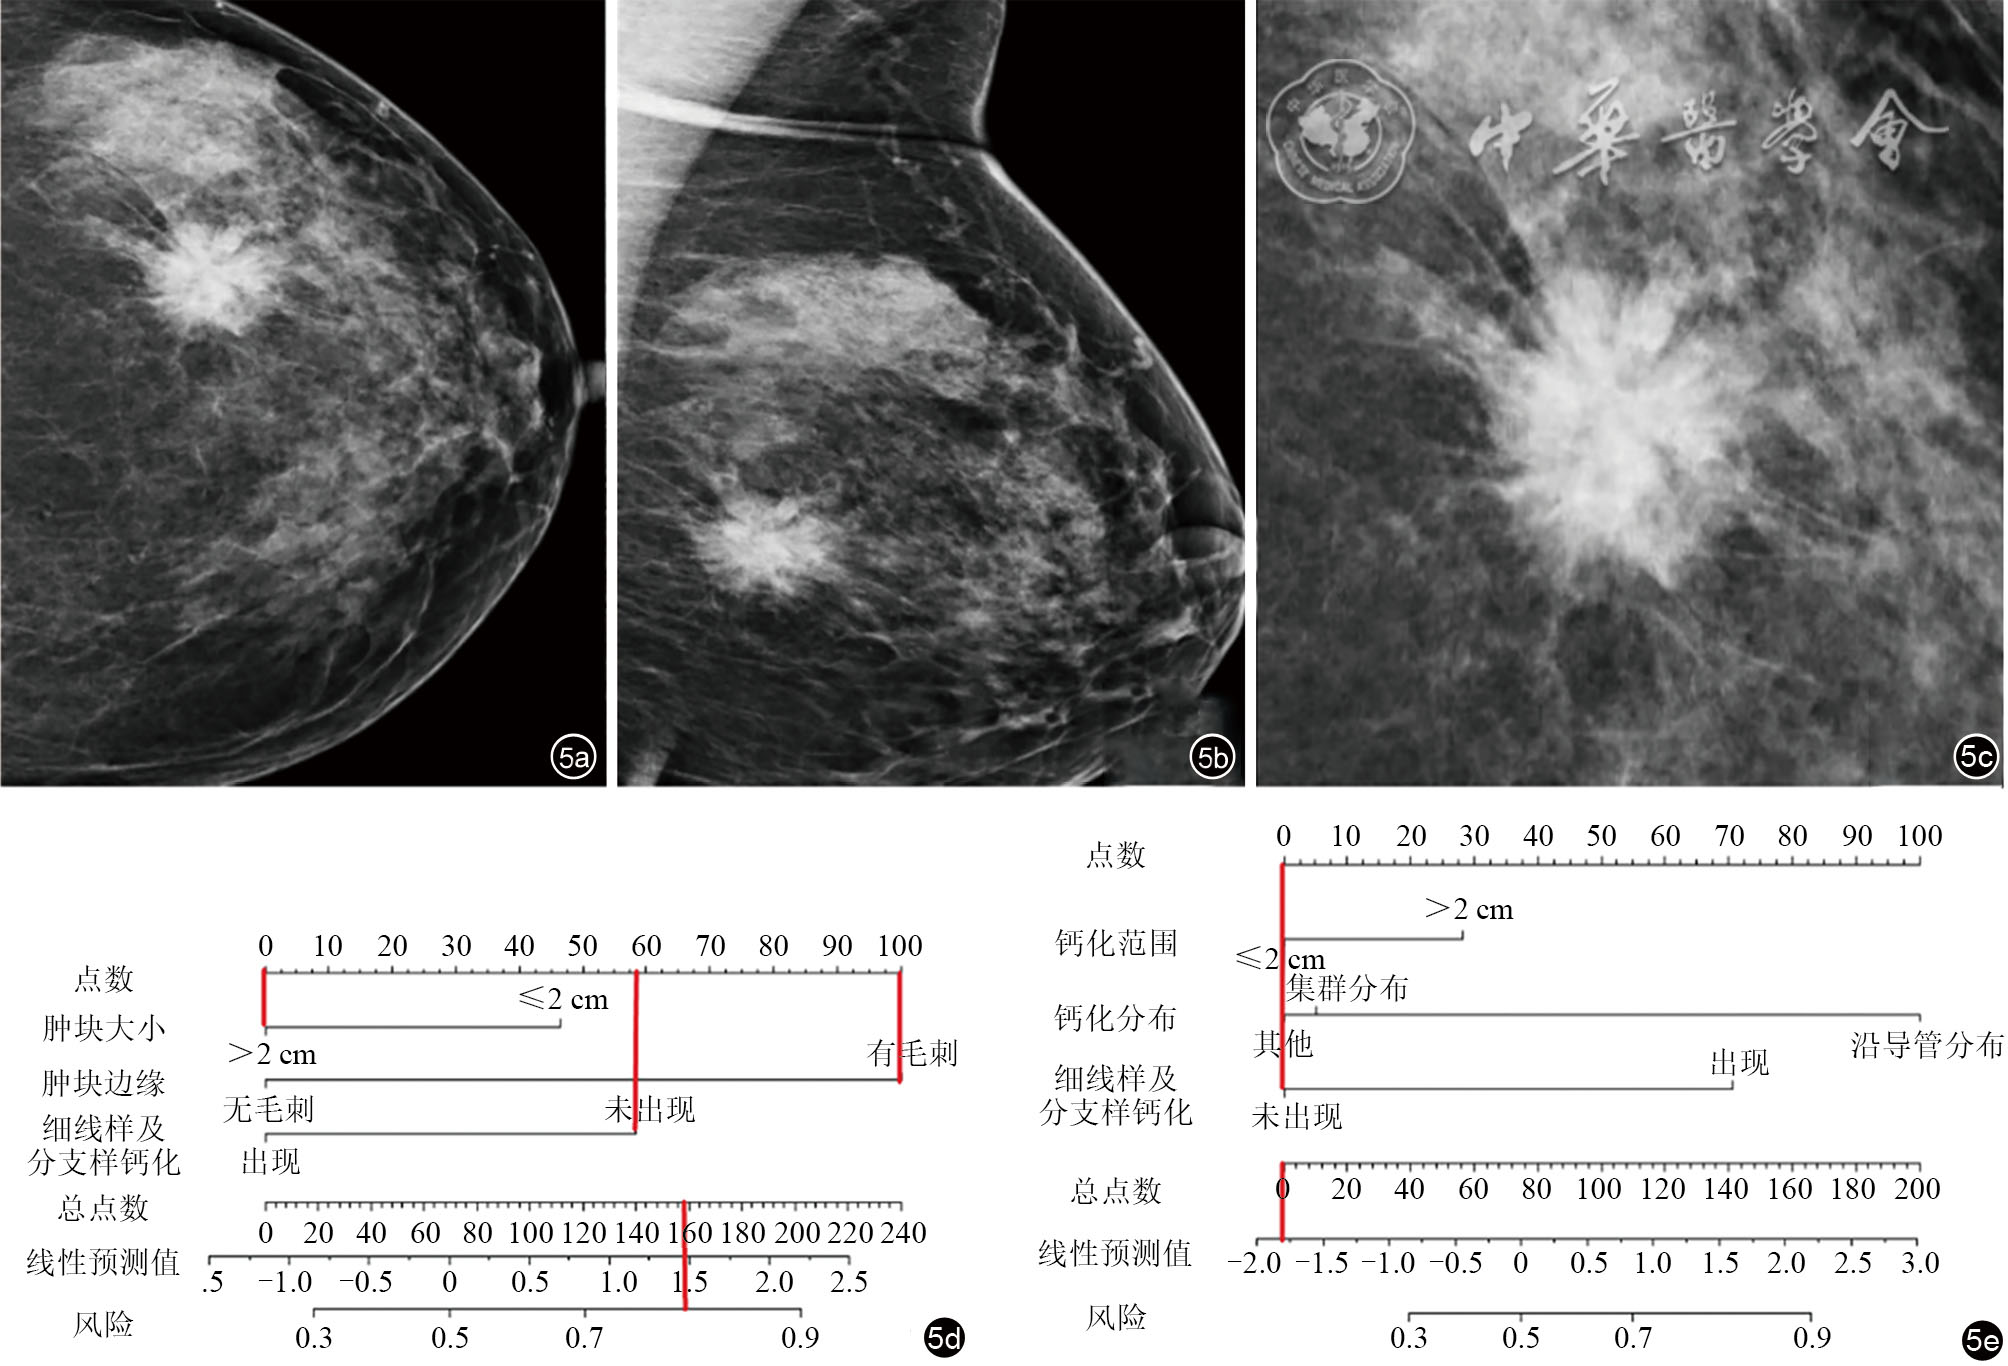

图5 乳腺HR阳性、HER2阴性病灶经X线联合列线图模型的预测及验证。图a为左乳头尾位;图b为左乳内外侧斜位;图c为肿块局部放大图;图d及e为HR和HER2联合预测模型预测此病灶HR阳性的可能性为80%,HER2阳性的可能性几乎为0